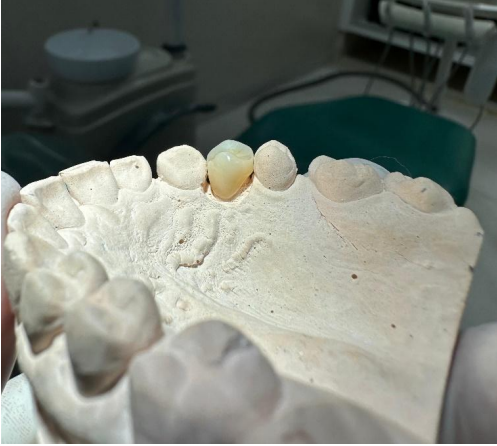

Figura – Modelo funcional em gesso

Figura – Coroa para teste clínico

2ª Sessão: Foi realizada a prova clínica da coroa confeccionada pelo laboratório, sendo posicionado e avaliado quanto à adaptação marginal, pontos de contato proximais, e oclusão. Foram feitas pequenas adequações, para ajuste oclusal, e reencaminhada ao laboratório protético para o processo final da coroa.